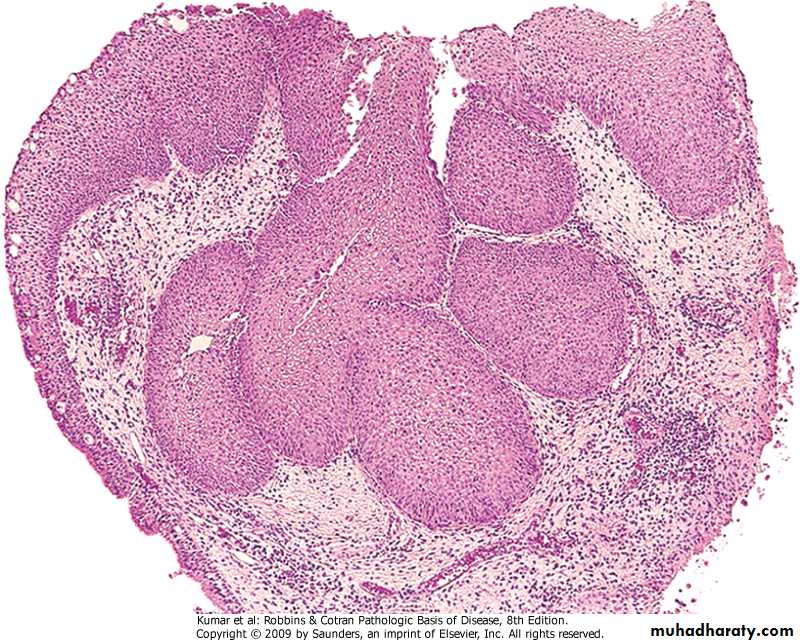

Microscopical: Bronchiectasis

Respiratory  System